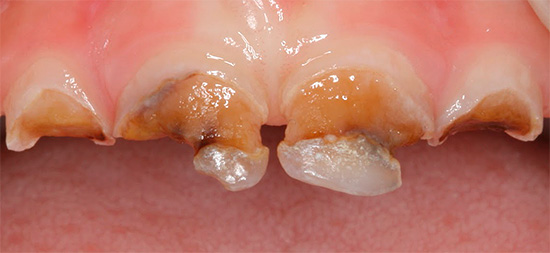

Immagini della bottiglia della carie:

Nell'aspetto e nella natura del corso, la carie delle bottiglie è quasi generalizzata. La principale differenza tra queste malattie è l'età delle persone che colpiscono: la carie in bottiglia si sviluppa principalmente nei bambini da 1 a 3 anni. Questo è spesso associato a un'immunità indebolita e malattie somatiche in tenera età.